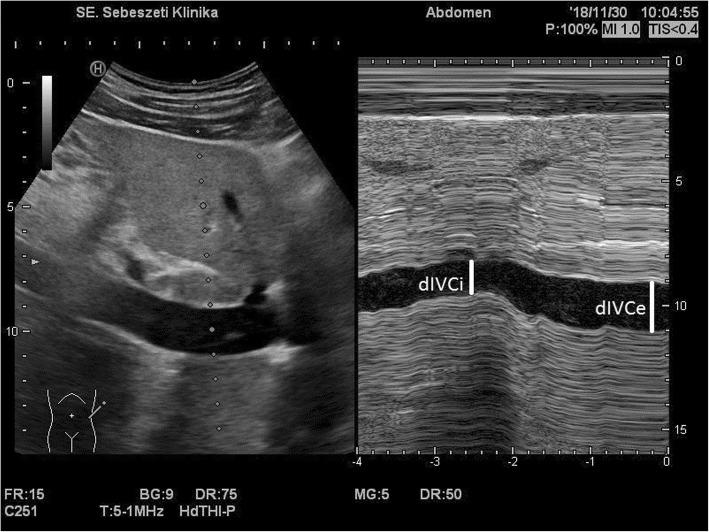

METHODS

A total of 102 patients undergoing elective general surgery under general anesthesia with standardized propofol induction were recruited for this prospective observational study. The IVCCI was measured under spontaneous breathing. A collapsing (IVCCI≧50%) (CI+) and a noncollapsing (CI-) group were formed. Immediate postinduction changes in systolic and mean blood pressure were compared. The performance of the IVCCI as a diagnostic tool for predicting hypotension (systolic pressure < 90 mmHg or a ≥ 30% drop from the baseline) was evaluated by ROC curve analysis.

术中低血压会增加 30 天死亡率以及心肌损伤和急性肾衰竭的风险。在麻醉诱导前储备容量不足的患者风险极高。因此,识别潜在的血容量不足至关重要。下腔静脉塌陷指数(IVCCI)的超声测量能够检测循环休克中的容量反应性。目前尚无证据表明术前测量 IVCCI 是否可以识别与全身麻醉相关的低血压高危患者。

方法

本前瞻性观察研究共纳入 102 例在全身麻醉下接受择期普外科手术的患者,采用标准化异丙酚诱导。在自主呼吸下测量 IVCCI。形成下腔静脉塌陷(IVCCI≧50%)(CI+)和不下腔静脉塌陷(CI-)组。比较诱导后即刻收缩压和平均血压的变化。通过 ROC 曲线分析评估 IVCCI 作为预测低血压(收缩压<90mmHg 或基线下降≥30%)的诊断工具的性能。